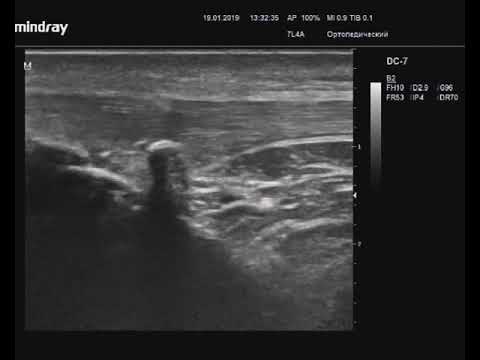

Кроме этого назначается УЗИ коленного сустава. Раннее выявление изменения сухожилий имеет большое значение в клинической практике, так как помогает провести консервативные методы лечения прежде, чем наступит разрыв.

Ультразвуковая картина тендинита собственной связки надколенника